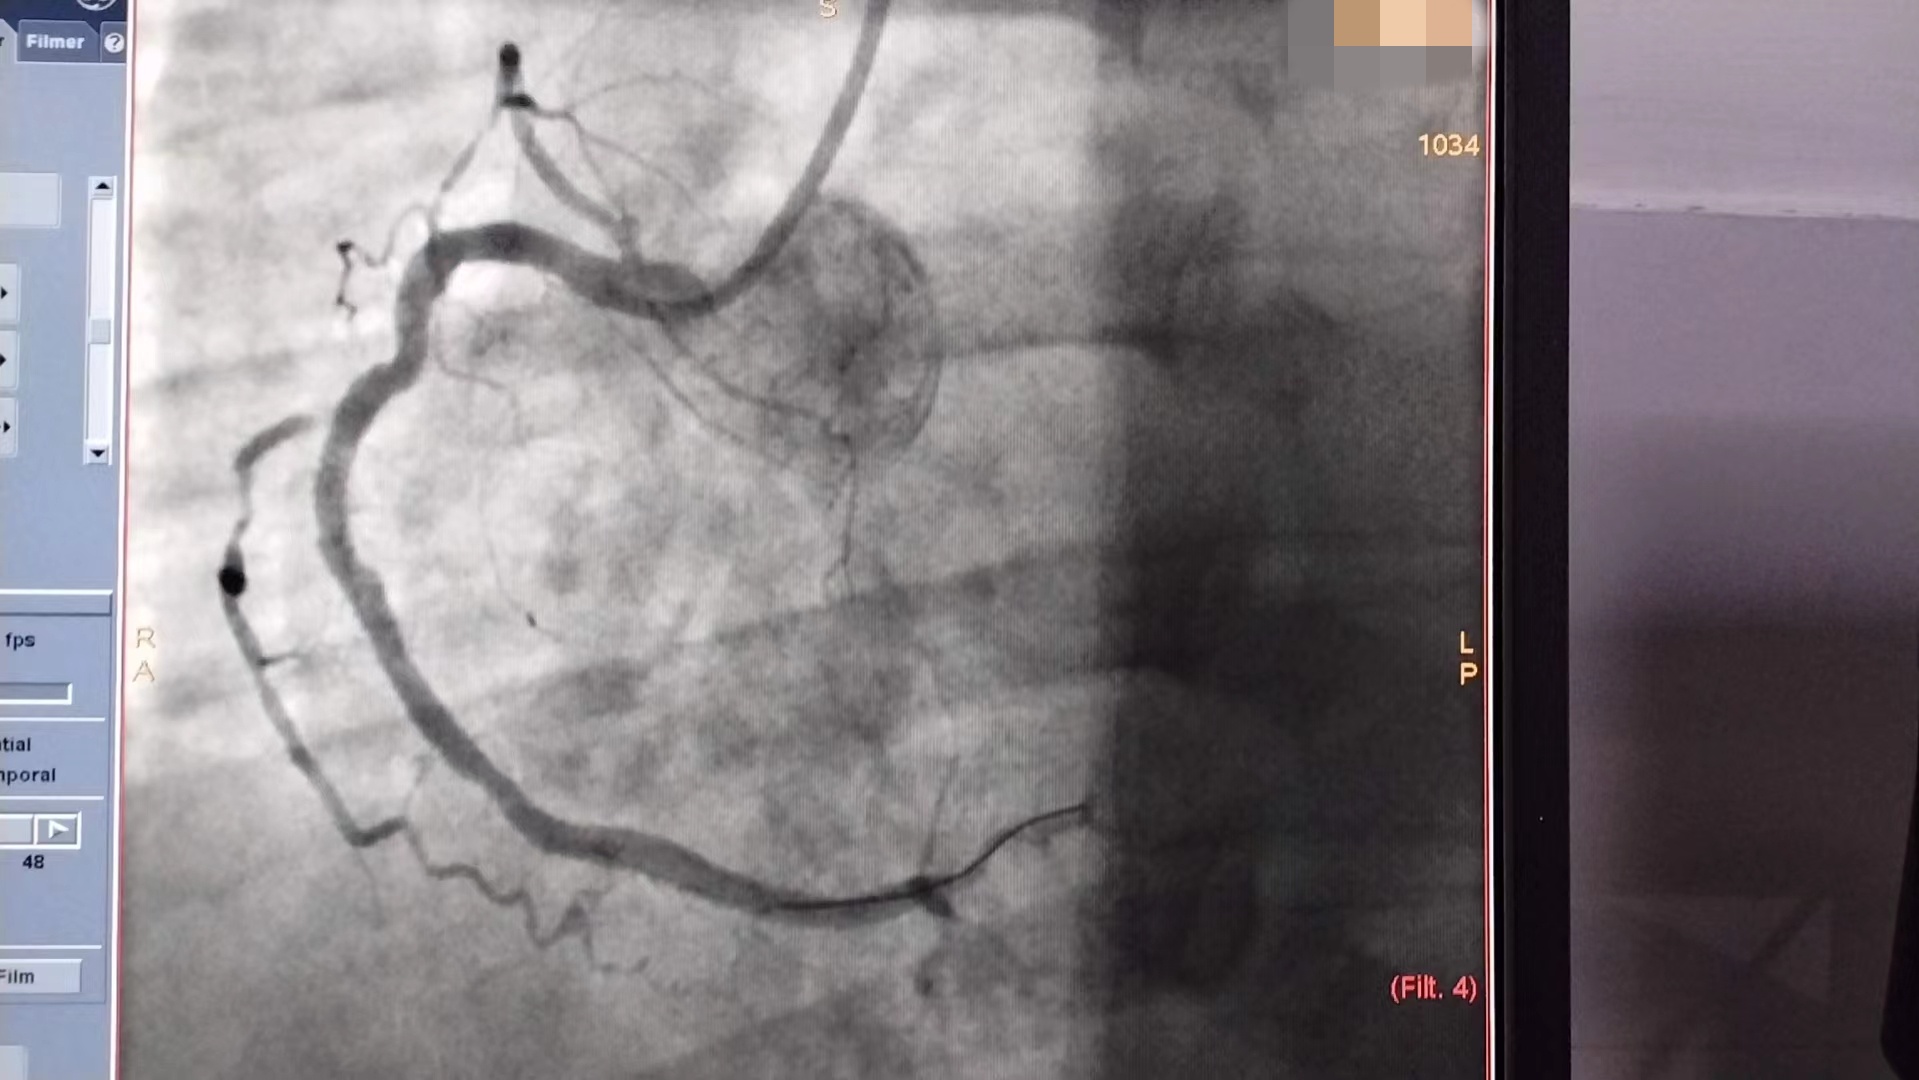

冠脉造影提示曾某右冠、前降支中段完全堵塞,病情相当危重,手术风险高,娄底市第二人民医院介入手术团队在曾某的充分信任和队员们的密切配合下,于90分钟内予以导丝通过闭塞血管、完成血运重建,至上午9点整顺利完成冠脉支架置入手术。术后曾某恢复良好。

术后